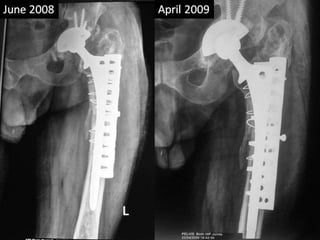

Case summary •Vancouver B3 type peri-prosthetic fracture • Revision THR for shattered femur by Mennen plate with non cemented Solution hip and bone grafting in acetabular wall defects. • Sciatic palsy • Removal of Mennen plate and wires in April 2009 after fracture union.

Surgery • Removalof implant. • Removal of cement from femur • Severe bone loss from acetabular walls • Iliac bone grafts were packed • Revision of acetabular cup was done and was fixed with three screws

• 13.

Surgery • Shaftpieces were approximated with cerclage wires over a solution stem. • A Mennen plate was used to hold the pieces together and further enforcement was done by few screws and wires. • Post op sciatic palsy. • Immobilization continued for 3 months